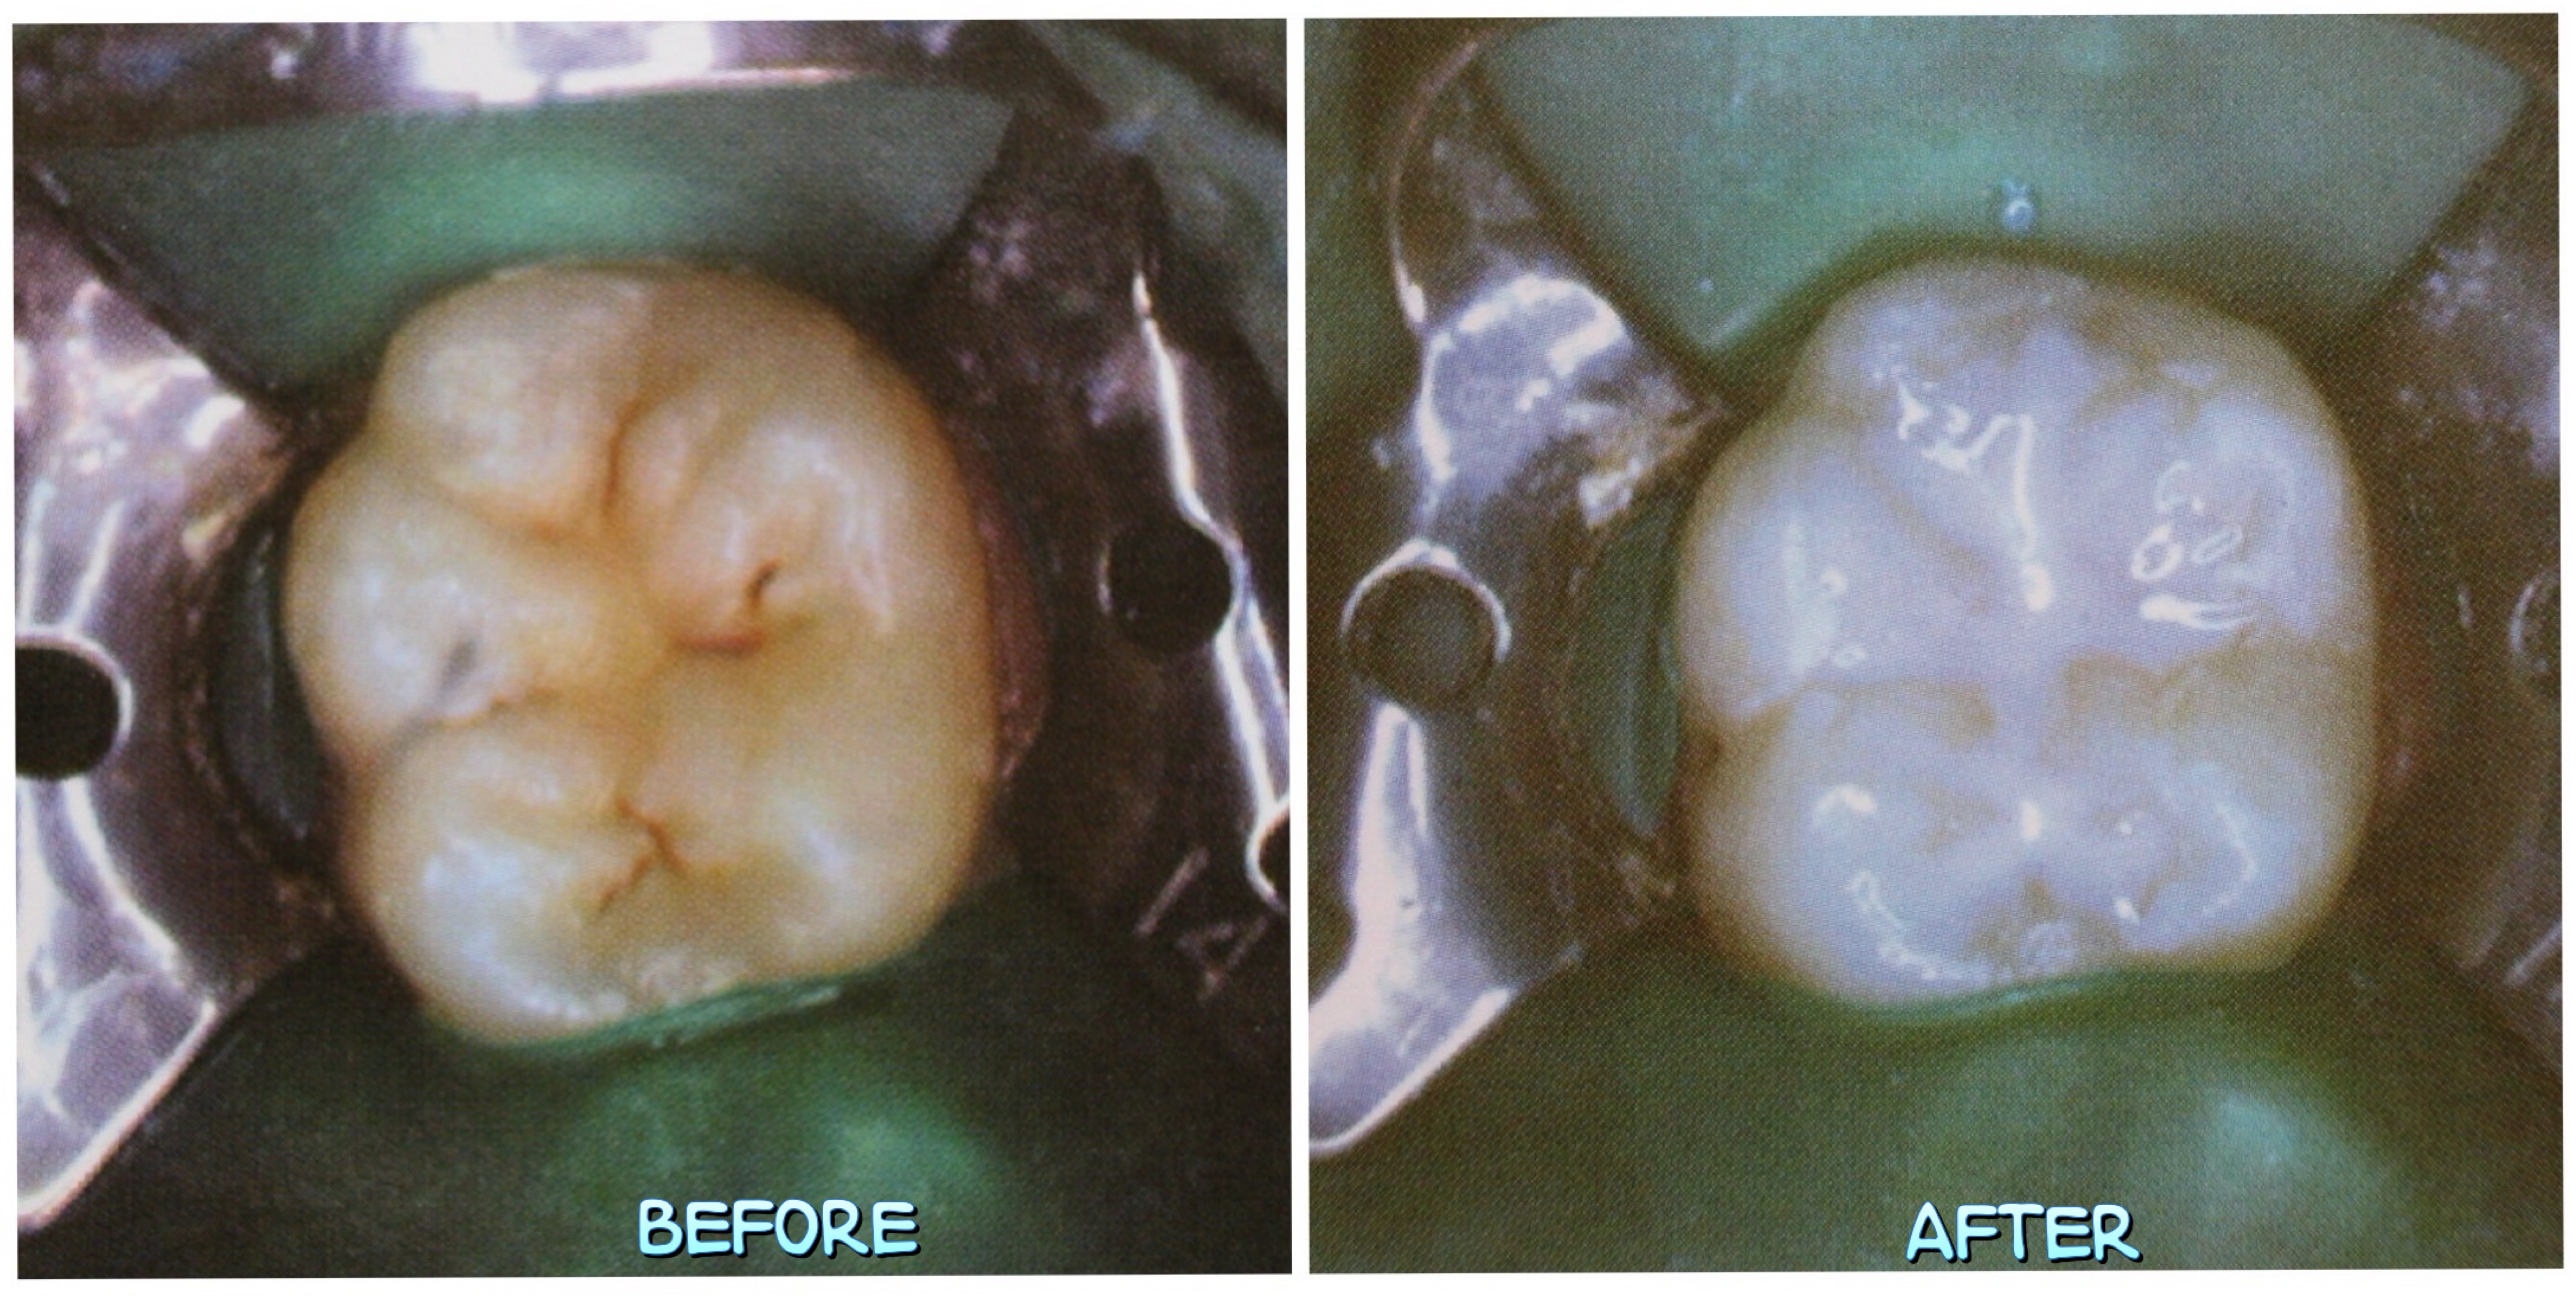

窩溝封填,Pit Fissure Sealant,在兒童牙科預防蛀牙的成效

兒童牙齒表面的咬合溝隙(pit and fissure)深且複雜,容易殘留食物殘渣及細菌,是蛀牙高風險區域。P… Continue reading

兒童牙齒表面的咬合溝隙(pit and fissure)深且複雜,容易殘留食物殘渣及細菌,是蛀牙高風險區域。P… Continue reading